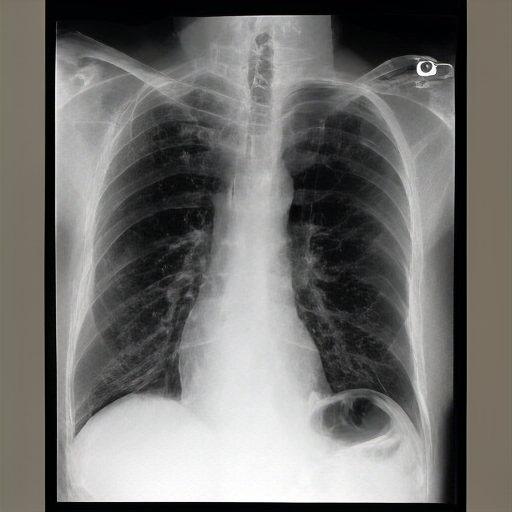

There are moderate-to-severe vascular congestion as well as perihilar opacification on the left than on the right. There is indistinctness of pulmonary vessels, suggestive of small-to-moderate pulmonary edema. There is no pneumomediastinum, a new small-to-moderate right-sided pleural effusion has not changed allowing for somewhat. There is no definite pneumothorax. A dialysis catheter has been removed.

Severe cardiomegaly is present. Previous mediastinal widening has improved. A region of consolidation, more discrete at the right base and in the left lower lobe, presumably with long-standing infection, is noted. There is increased vascular engorgement. No pulmonary edema is seen. Mediastinal vascular engorgement is present. A dual-channel hemodialysis catheter is at the cavoatrial junction, and atrial node tubes are in place.